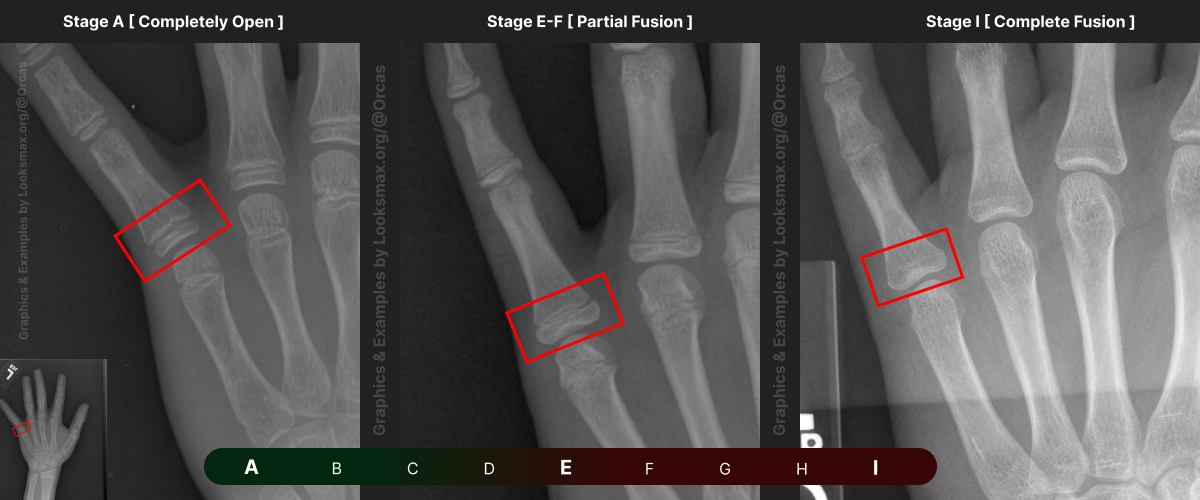

I added references for stages A (Completely unfused), E-F (Partial fusion, basically late stages of puberty), and I (Complete Fusion)

You will have to eyeball this now using your own xrays, I’ve given three examples and some wiggle-room for letters using a reference bar (green-red) below the image, write down your estimated guesses in a text file until you finish all 13 bones.

Don’t doubt yourself, eyeballing isn’t perfect but it still works well, just choose & continue.

Ex.

“My Radius looks more fused than the image from E-F, but its not as fused as I, it’s closer to the 2nd picture though, so I’ll rate it G” And continue

Bonetype: 1st Metacarpal (thumb)

Check & use the chart below to figure out where you are. Then write your result on a piece of paper or a text file.